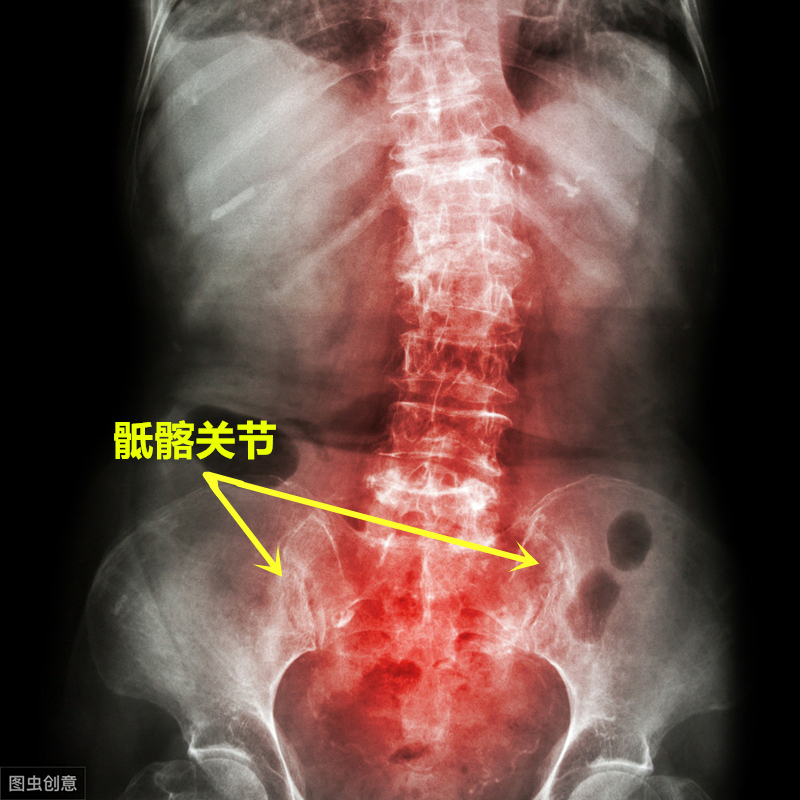

强直性脊柱炎是一种慢性炎症性疾病,主要侵犯骶髂关节,一般这种炎症从骶髂关节开始,逐渐向上发展至腰椎、胸椎及颈椎,出现相应部位的疼痛,严重者可发生脊柱畸形和强直。

强直性脊柱炎